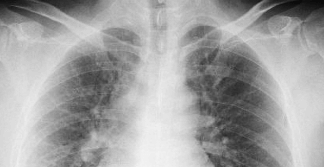

• レントゲン

胸部レントゲン検査

心不全や心臓肥大、大動脈瘤などの循環器疾患、肺炎や肺気腫、肺結核、肺がんなどの呼吸器疾患の診断を行います。